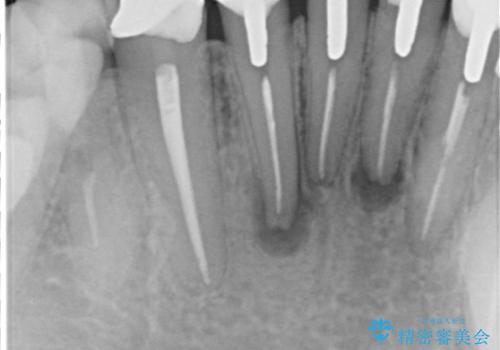

根っこに病気があり、根管治療から被せ物まで治療を行いました。

根管治療を行った後、3ヶ月間治癒の確認をしてからオールセラミックスペシャルで治療を行いました。

- 根管治療により痛みや腫れがひかない事や、術後に痛みや腫れが生じる事、治療によるファイル破折やパーフォレーションなどの偶発症、術後の歯根破折を生じる可能性もあります